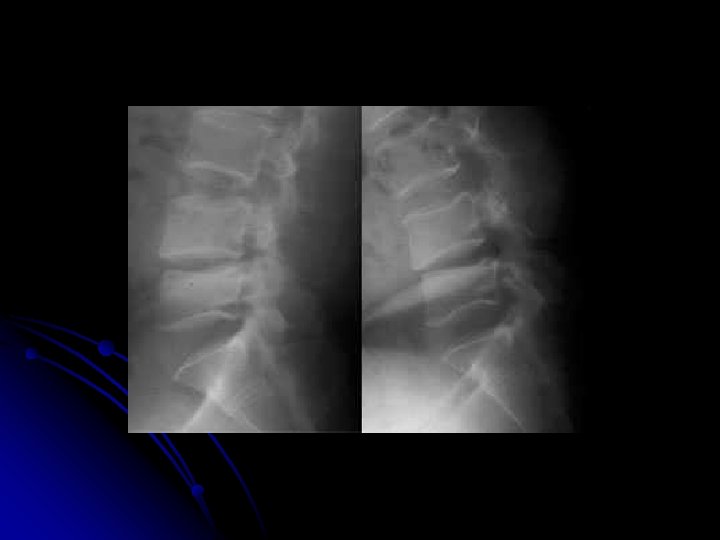

l Clichés dynamiques l Profil l Position même que pour le profil d'ensemble/ l l Flexion maximale, sans aide et sans dépasser le seuil douloureux l Extension maximale sans aide et sans dépasser le seuil douloureux Centrage, rayon directeur, et critères de réussite, sont identiques au profil d'ensemble l Précautions: l Patient conscient l Médecin présent l Absence de contre-indication neurologique l Un délai de 10 à 15 jours par rapport au traumatisme est habituellement à respecter.

Neutre Flexion Extension

Traumatisme l RX standards l Clichés dynamiques (rachis cervical): recherche d'une instabilité postérieure l l TDM avec reconstructions multiplanaires: l bilan d'une fracture instable l Fracture du mur postérieur l luxation d'une articulation postérieure IRM: l lésion médullaire l fracture pathologique l hernie discale

Malformations, scoliose l RX standards (2 segments au moins, cervicale+dorsale ou dorsale+lombaire, ou colonne totale); mesure des angles de scoliose l l Clichés dynamiques: l stabilité ou fixité d'une scoliose, l stabilité ou fixité d'une hypercyphose ou d'une hyperlordose IRM: l malformation de Chiari, l hydromyélie, l moelle attachée, l lipome sacro-coccygien, l méningocèle CT: l malformations vertébrales complexes, diastématomyélie l contrôle post-opératoire (éléments métalliques empêchant la réalisation d'une IRM) Échographie (petits enfants): défauts de fermeture de l'arc postérieur et moelle attachée